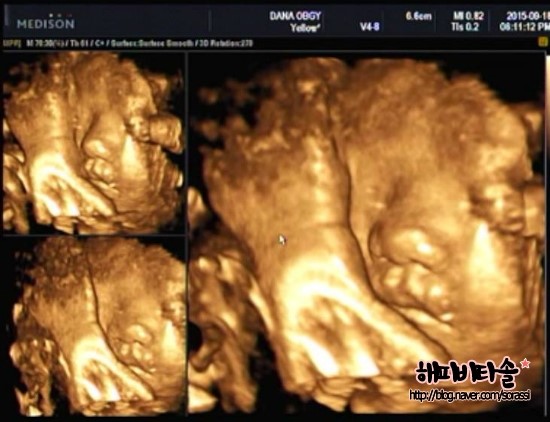

[임신 31주+2일] 쑥쑥이의 입체 초음파, 임산부 백일해 / 독감 주사

[임신 31주+2일] 쑥쑥이의 입체 초음파, 임산부 백일해 / 독감 주사 <일자> 2015...